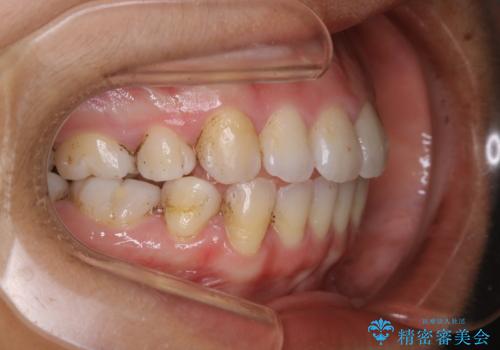

タバコをよく吸う方で1年ぶりのクリーニングになるそう。ただ、昔から着色が付きやすく取れないとのこと。

エアフローを使いましたが、汚れはとても頑固で、元々歯の面に多くの凹凸があり、その隙間に入り込んでいる着色、虫歯の初期による変色以外を除去していきました。60分でも時間は足りませんでした。